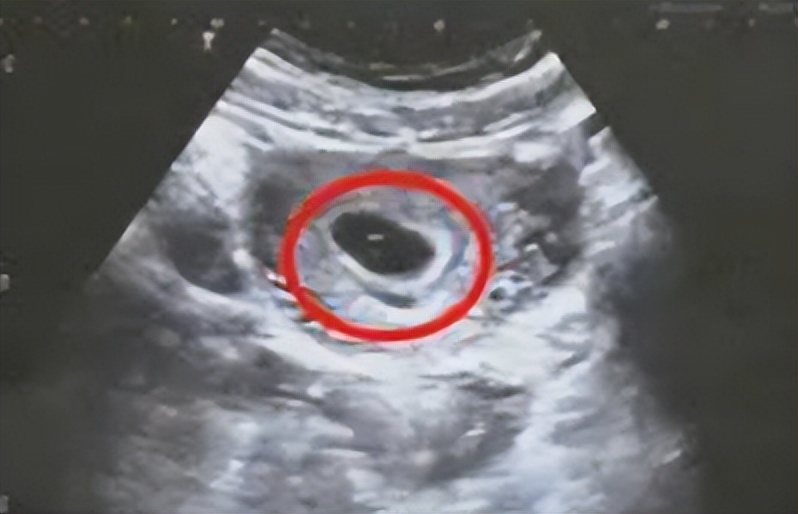

有些女性完全无症状,是在B超下发现胚胎的异常表现: B超下能看到孕囊,却没有卵黄囊,没有胎芽、胎心。

临床上表现为在如果孕囊直径>20mm,而囊内仍未见到胚芽,则提示空囊。